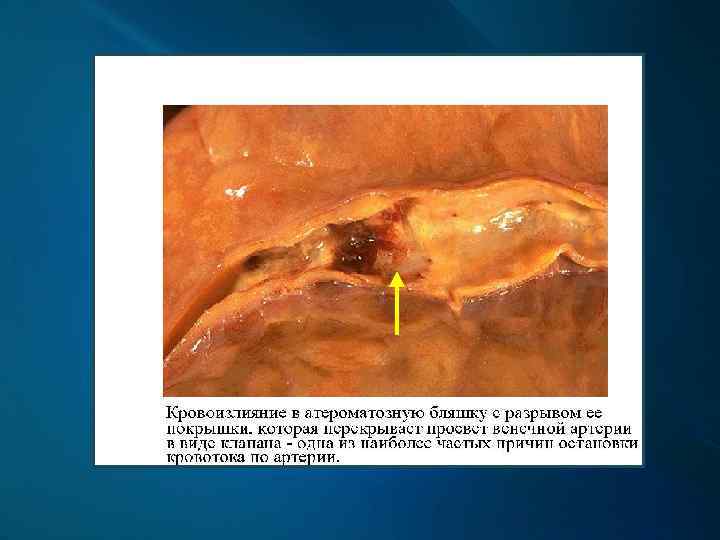

Патогенез и морфогенез атеросклероза 1. 2. 3. 4. 5. 6. 7. Накопление в интиме артерий гликозаминогликанов и мукоидный отек, повышение проницаемости эндотелия и мембран интимы (долипидная стадия). Очаговое накопление в интиме холестерина, липопротеидов и белков (липоидоз). Превращение макрофагов и гладкомышечных клеток артерий в пенистые (ксантомные) клетки за счет накопления в них липидных продуктов. Пролиферация и последующее созревание в стенке артерии фибробластов и др. биоактивных веществ, выделяемых активированными ксантомными клетками (липосклероз). Распад ксантомных клеток и липидных масс, гладких миоцитов средней оболочки (атероматоз). Разрыв покрышки бляшки с образованием пристеночных тромбов (изъязвление или язвенный атероматоз). Очаговое обызвествление атероматозных масс (атерокальциноз).

Клинические проявления и осложнения Атеросклероз венечных артерий сердца проявляется их стенозом, вызывающим приступы стенокардии, осложняется развитием инфаркта миокарда.